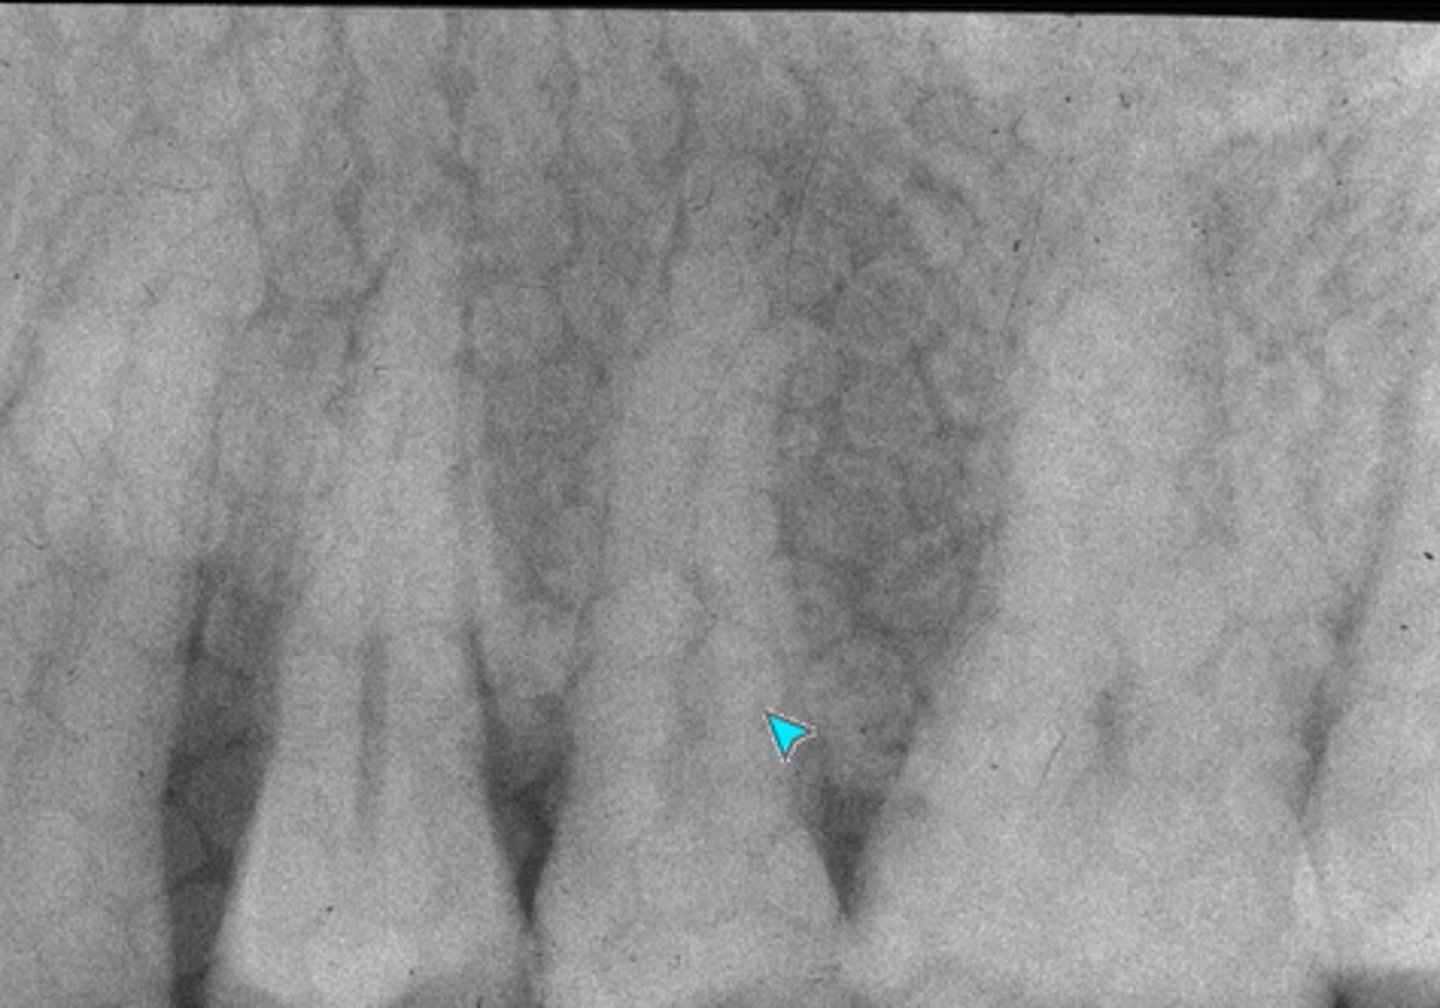

What error occurred here?

Film exposed backwards

What error occurred here?

Double exposure